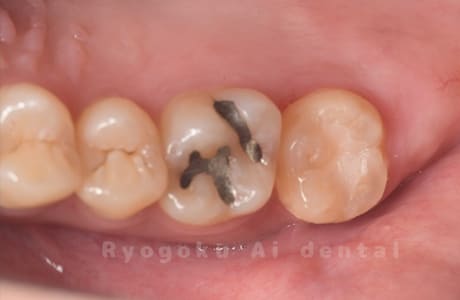

Case27

-

重度カリエス

歯牙移植咬合面術前 -

移植する親知らず

歯牙移植術直後咬合面

歯牙移植術後咬合面

歯牙移植術前側面

歯牙移植術中側面

歯牙移植術後側面

- 原因

- 重度カリエス

- 治療内容

- 自家歯牙移植、部分矯正

- 治療費用

- 220,000円(移植費用)

110,000円(部分矯正費用)

虫歯が大きく、保存不可能となった歯を上の親知らずと交換する自家歯牙移植を行いました。移植歯が小ぶりであったため、部分矯正を行い問題なく噛み合い、経過良好です。